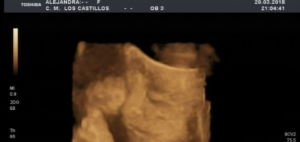

Llaman al teléfono SOS de +Futuro. Son las 11 de la noche, son un grupo de misioneras de extremadura. Acogen y educan a chicas desahuciadas y en riesgo de exclusión social. Una de sus chicas, ya mayor de edad que se ha ido a vivir con la madre de su novio esta de 26 semanas de embarazo. Quieren que aborte todo su entorno. Ella no. Un médico y el abortorio «Los Arcos» de Badajoz dicen que su niño viene con hidrocefalia. Afirman con contundencia que la madre corre peligro de morirse. (fotos de una ecografía de Alexia, la hija de dos voluntarios de la asociación de 26 semanas).